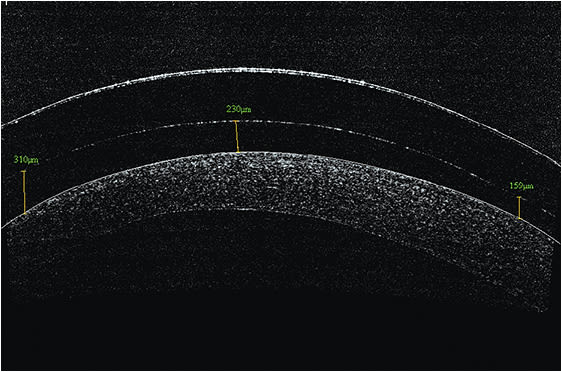

Fitting scleral lenses is typically done by selecting the best sagittal height match between the cornea and the contact lens. The desired central vault over the corneal surface varies according to lens design and the clinicians’ desired fitting philosophy for each individual patient. Typical values will range from about 150 to 400 microns. Figure 1 shows an example of excessive sagittal vault. Figure 2 shows an example of insufficient vault. And, Figure 3 shows an example of a desired amount of vault. Note: Scleral lenses settle into the bulbar conjunctiva over time following application. As such, central vault values can decrease by as much as 100 to 200 microns over a few hours after application.

Figure 3. Sagittal height of 159 to 310 μm = desired amount of vault.